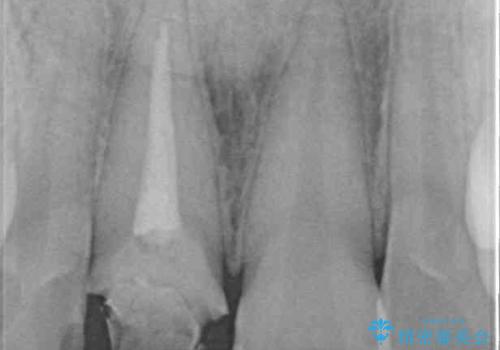

土台に含まれている金属も含め、口腔内の金属は全て除去し、根管治療が必要な歯は根管治療を行い、オールセラミッククラウンやセラミックインレーにて治療することとしました。

途中来院されない時期があったため、初診から終了まで期間がかかりましたが、根管治療を行った歯の根尖病変はいずれも改善を確認することができました。